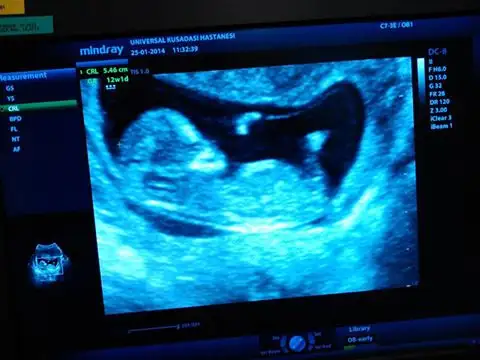

herkese merhaba, bebeğim burada tam 12 haftalık. ikili test için gittiğimde alındı bu görüntü. doktor %50 kız %50 erkek dedi sağolsun. buradan okuduklarım kadarıylada nub göremedim sanki bacak arasında kalmış gibi geldi. çok da merak eiyorum. yorumlarınızı bekliyorum. Eki Görüntüle 976147